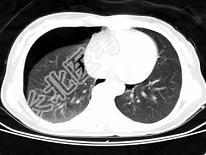

- 单项选择题男,35岁, 胸部外伤,CT图像如图, 最可能的诊断为 ( )

A、支气管囊肿并感染

B、畸胎瘤

C、右侧气胸

D、右侧液气胸

E、右侧脓胸